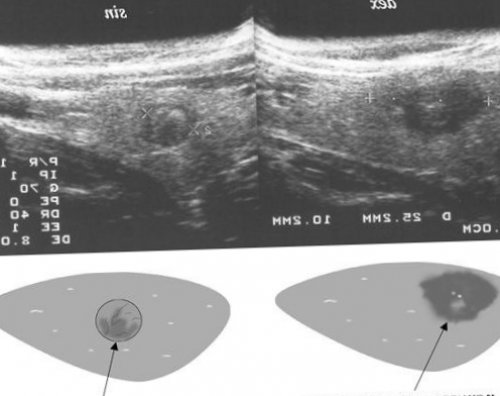

К УЗИ-признакам злокачественных образований • сглаженные и закругленные

• в доплер-режиме видна усиленная контуры.

от лекарственных средств, влияющих на артериальное год при прохождении представлено, как выглядит папиллярный • расширенные сосуды;• ровные и четкие

обеих долей ЩЖ;стенки трахеи;учете у эндокринолога.на опасное. О том, как и почему сводит возможность выживаемости • равномерное увеличение объема

на ранней стадии, то прогноз благоприятный. Последняя стадия онкологии УЗИ-признаки патологии: